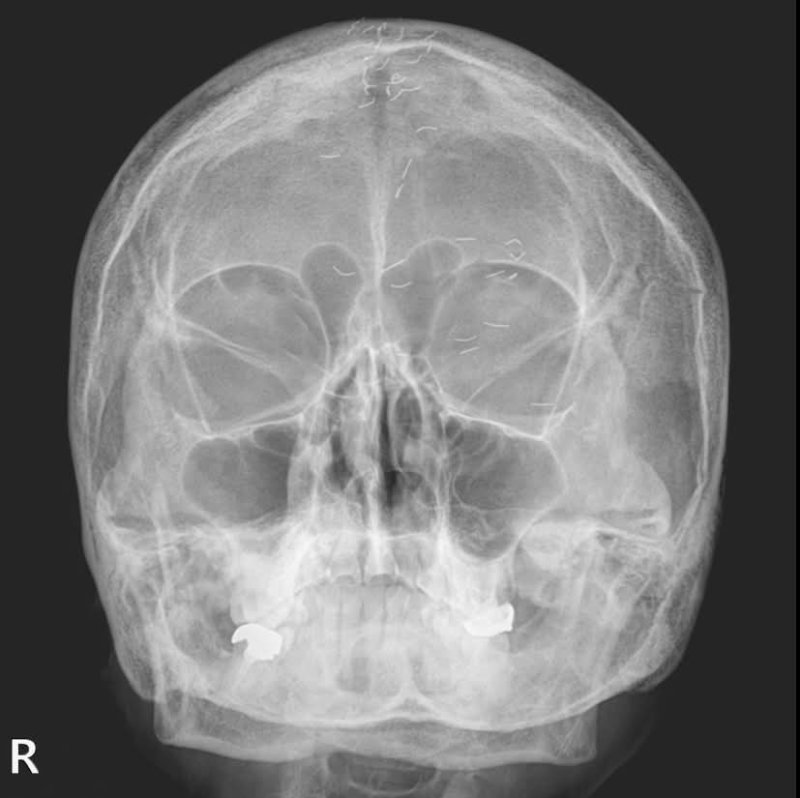

양성관 의정부백병원 가정의학과 과장이 SNS에 공개한 60대 여성 환자의 머리 엑스레이 사진. (양성관 의사 페이스북 캡쳐)/뉴스1

(의정부=뉴스1) 양희문 기자 = 60대 한국 여성 머릿속에 기생충처럼 보이는 수많은 이물질이 흩어져 있는 엑스레이 사진이 공개됐다. 이는 얇은 순금을 통증 부위에 주입하는 '금침요법'으로 인해 생긴 것으로, 이물질이 남아 있는 상태에서 시행할 경우 염증 악화와 2차 감염으로 이어질 수 있다.

양 과장은 "60대 여성 환자의 엑스레이에 1㎝ 크기의 수많은 이물질이 보였다"며 "기생충인가? 전기칩인가? 외국이었다면 특이한 환자 사례로 올랐을 것"이라고 적었다. 이어 "하지만 한국 의사라면 보자마자 헛웃음을 짓는다"며 "이물질의 정체는 기생충이나 전기선이 아니라 금침 자국이었다"고 했다.

금침요법은 금실매선요법을 말한다. 얇은 순금을 1cm 미만의 길이로 등분한 뒤 통증 부위에 주입하는 치료법이다. 한 번 주입한 금실이 해당 부위를 지속해서 자극해 치료 효과를 높인다고 한다. 그러나 몸속에 잔여 이물질이 남아 있으면 염증 악화와 2차 감염 등으로 이어질 수 있다.

양 과장은 해당 환자에게 '긴장성 두통' 진단을 내렸다. 그는 "뇌 MRI(자기공명영상)와 MRA(자기공명혈관영상) 검사는 정상이었고, 출혈·뇌암·뇌경색은 확실히 아니었으니 긴장성 두통이 확실했다"며 "환자에게 너무 걱정하지 말라고 했다"고 전했다.